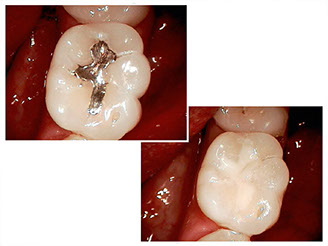

Successful treatment of a complicated molar with four canals by Dr. Young

• Root canal treatment

Advances in the field of root canals have led to effective, consistent, and predictable results.

Treating a tooth with a root canal involves removing and shaping the inner portion of a tooth, cleaning and disinfecting the root canal spaces, and filling the roots.